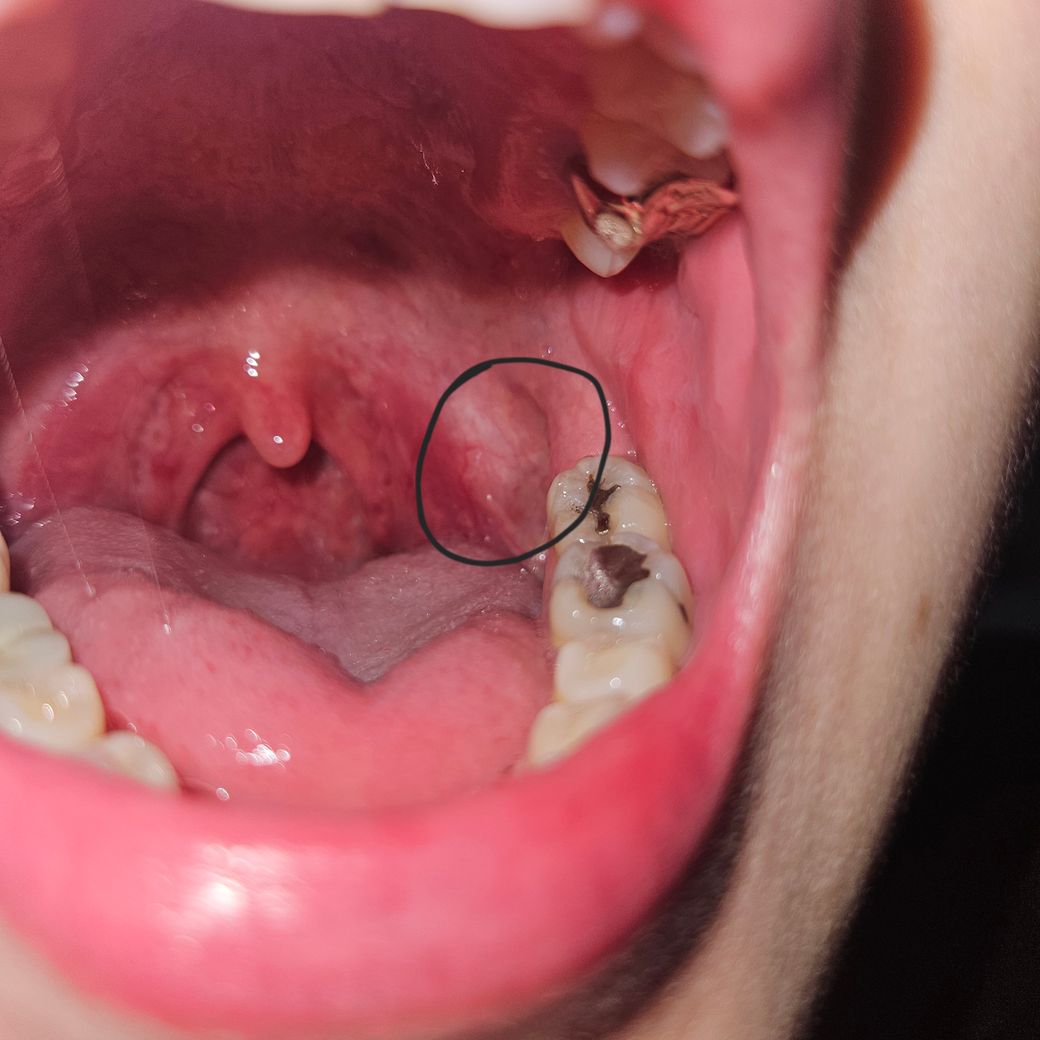

사진이 편도가 부은건가요??ㅠㅠㅠ

사진처럼 왼쪽 입안 편도 옆쪽인데 오른쪽은 괜찮은데 왼쪽만 부었어요..이게 입을 아 하고 벌리면 왼쪽만 튀어나오는데 뭐때문에 이런걸까요?? 저 표시 명칭은 뭔가요?? 그냥 피곤해서 부은걸까요?? 아님 처음부터 저렇게 생긴걸까요??ㅠㅠ